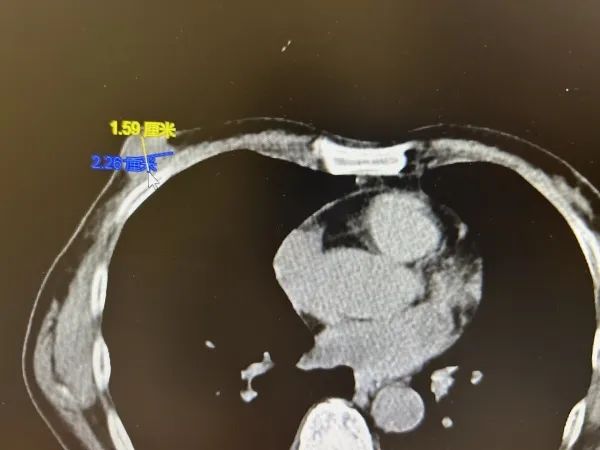

影像报告显示,张老伯的右乳有一个直径约为2厘米的肿块,初步诊断考虑为乳腺恶性肿瘤,如果不及时手术切除,可能会进一步进展转移。医生迅速为张老伯进行了乳房肿块切除活检手术,经快速病理检查,确诊是乳腺癌 。

影像报告显示张老伯的右乳有一个直径约为2厘米的乳腺恶性肿瘤